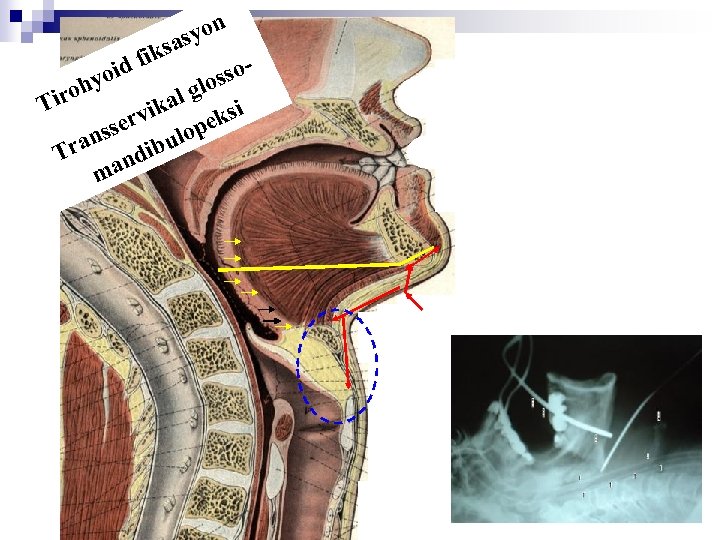

n Dil kökü rezeksiyon cerrahisi ¨ Transservikal dil kökü rezeksiyonu ¨ Intraoral dil kökü rezeksiyonu ¨ (RF n uygulamaları) Dil kökünün kollapsını önleyen operasyonlar ¨ (RF Uygulamaları) ¨ Hyoid n n fiksasyon ameliyatları Thyro-hyoid fiksasyon Hyoid – mandibula fiksasyonu ¨ Sleep-in n tekniği Transservikal glosso-mandibulopeksi yusufk@gazi. edu. tr

n syo a iks id f o sso y glo roh l Ti i ika erv opeks nss bul Tra ndi ma a yusufk@gazi. edu. tr